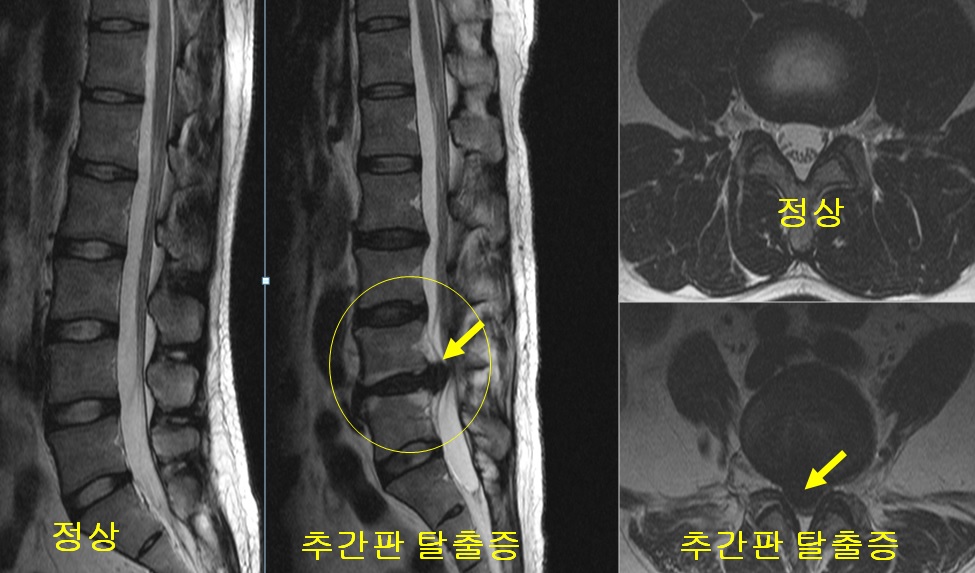

디스크 탈출: 디스크 손상으로 인해 디스크의 내부 젤 상태 물질이 디스크의 외부를 벗어나는 경우를 말합니다.

디스크 탈출은 인근 신경을 압박하거나 디스크 조각이 신경근에 침범하여 발생하는 통증, 저림, 근육 약화 등의 증상을 유발합니다.

척추 디스크 질환의 진단은 종종 신체검사와 환자의 증상 및 병력을 바탕으로 합니다. 추가적인 검사는 X선, MRI, CT 스캔 등을 포함할 수 있습니다.